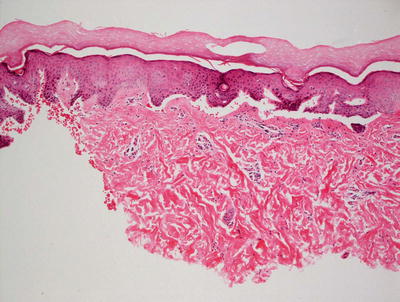

3.13.2 Histology

The histologic changes in dystrophic epidermolysis bullosa are largely indistinguishable from those seen in the junctional variant. A non-inflammatory subepidermal blister is present with no other alterations in the epidermis [92]. In contrast to the junctional form of epidermolysis bullosa, prominent dermal scarring may be present, especially if the biopsy is taken from an area of repeated blistering. In these cases, there may be a slight inflammatory response within the dermis secondary to repeated ulceration and healing; however, the inflammation is reactive and not part of the primary disease process (Fig. 3.33). Ultrastructural studies demonstrate the presence of blister formation deep to the lamina densa due to reduction (dominant forms) or absence (recessive forms) of anchoring fibrils comprised of type VII collagen [119–122].

Fig. 3.33

Recessive dystrophic epidermolysis bullosa demonstrates a subepidermal blister with some lymphocytic inflammation